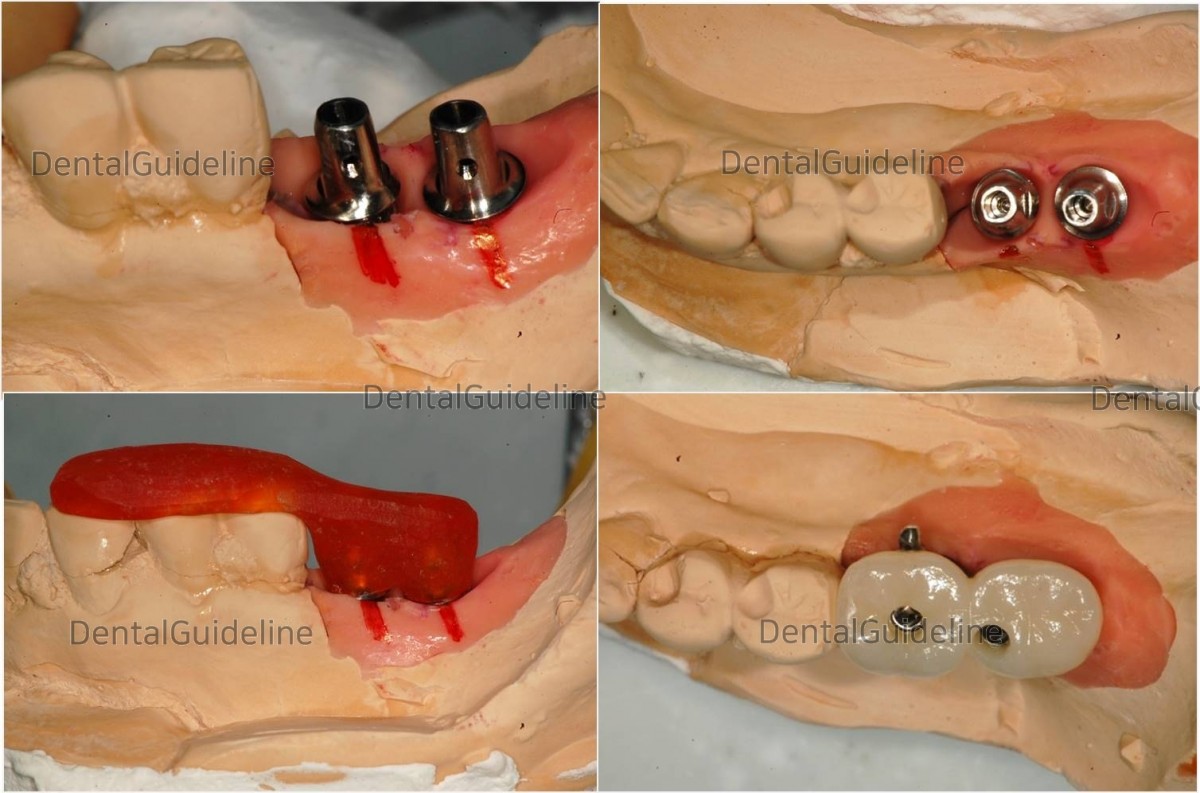

lab work.

screw hole sealing![]()

Porcelain Fused to Metal crown.![]()

Porcelain Fused to Metal crown.